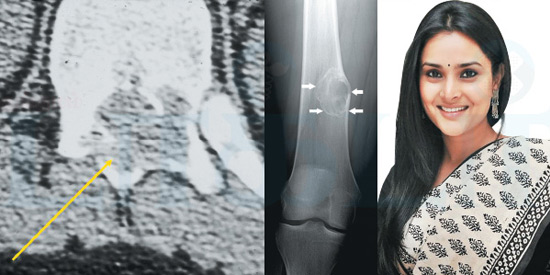

திவ்யா ஸ்பந்தனா என்ற பெயரில் தற்போது அறியப்படும் கர்நாடகாவைச் சேர்ந்த நடிகை ரம்யா தமிழிலும் ரசிகர்களுக்கு நன்கு அறிமுகமானவர். அரசியலில் பிஸியாக இருந்த ரம்யா, சமீபகாலமாக எந்த பொது நிகழ்ச்சியிலும் கலந்து கொள்ளவில்லை. கர்நாடக தேர்தலின்போது ஓட்டுப் போடுவதற்கும் வரவில்லை.

தனது காலில் ஆஸ்டியோ ப்ளாஸ்டோமா என்ற எலும்பு சார்ந்த முள்ளந்தண்டு நோய் ஏற்பட்டுள்ளதாகவும், காலில் சிகிச்சை மேற்கொண்டு கட்டுப் போடப்பட்டிருப்பதாகவும் படத்துடன் குறிப்பிட்டுள்ளார். அதன் கீழ் பொதுமக்களுக்கு விழிப்புணர்வு ஏற்படுத்தும் வகையில் ஒரு குறிப்பும் எழுதியிருந்தார். ‘கடந்த அக்டோபர் மாதம் முதல் நான் ஆஸ்டியோப்ளாஸ்டோமா நோயால் பாதிக்கப்பட்டுள்ளேன். இதற்காக சிகிச்சை பெற்று வருகிறேன். பாத எலும்புகளில் வலி கடுமையாக உள்ளது.

ஆஸ்டியோப்ளாஸ்டோமா(Osteoblastoma) என்பது எலும்புப்பகுதியில் உருவாகும் ஒருவகை கட்டி. இந்த கட்டி புற்றுநோயாக மாறும் அபாயம் கொண்டது. முதுகெலும்பு, கால்கள், கைகள் மற்றும் பாத எலும்புகளில் உருவாகக் கூடியது. வளர் இளம்பருவத்தினரை அதிகம் பாதிக்கக் கூடியது ஆஸ்டியோப்ளாஸ்டோமா. குறிப்பாக, 10 வயதில் இருந்து 30 வயதுக்குட்பட்டோரை அதிகம் பாதிக்கிறது.

உடலில் வலி இருக்கிறது என்று சொன்னால் உடல் பரிசோதனையில் மருத்துவர் கண்டுபிடித்துவிடுவார். எலும்பு பகுதி மென்மையாவது, வலி பரவுவது போன்ற விஷயங்களை வைத்து கண்டுபிடிப்பார். தசைகளைப் பரிசோதனை செய்வதன் மூலமும் ஆஸ்டியோப்ளாஸ்டோமாவை கண்டுபிடிக்க முடியும். எக்ஸ் ரே, சி.டி.ஸ்கேன், எம்.ஆர்.ஐ மூலம் அடர்த்தியை கண்டுபிடிப்பதன் மூலம் ஆஸ்டியோப்ளாஸ்டோமாவை தெரிந்துகொள்ள முடியும்.